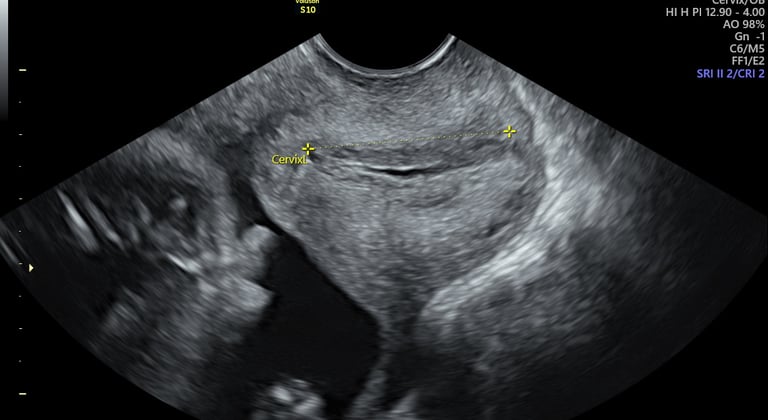

cervicometría